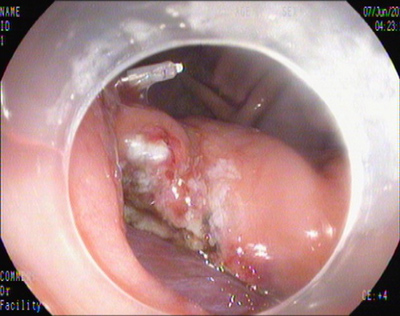

胃镜下切除术

2014年7月4日,田俊斌医师施行全身麻醉,李雪荣、左爱丽护师等为手术护士,邹百仓主治医师、张莉主治医师施行EFTR手术。胃镜下见胃底体交界前壁见巨大粘膜下肿瘤,暴露于胃腔的瘤体大小约3.0×4.0cm,表面光滑,中央凹陷。粘膜膜下注射后,环形切开瘤体周围粘膜,剥离瘤体周围粘膜下层,中央与肌层紧密连接,并向腔外生长,全层切开瘤体周围肌层,完整切除瘤体,可见腹腔脏器及网膜组织,钛夹尼龙圈荷包缝合切口,尼龙圈脱落,后用钛夹夹闭缝合切口,创面无渗血。由于标本较大坚硬无法完整一次取出,用圈套器将瘤体分切成5块,分块取出,拼凑复原瘤体形态,测量大小4.0×5.0cm。术后4天胃镜复查:胃壁切口溃疡形成,无出血及穿孔,嘱患者进食流质饮食。病理结果:胃底间质瘤,中、低度恶性风险,向神经纤维瘤发展。术后1周出院。